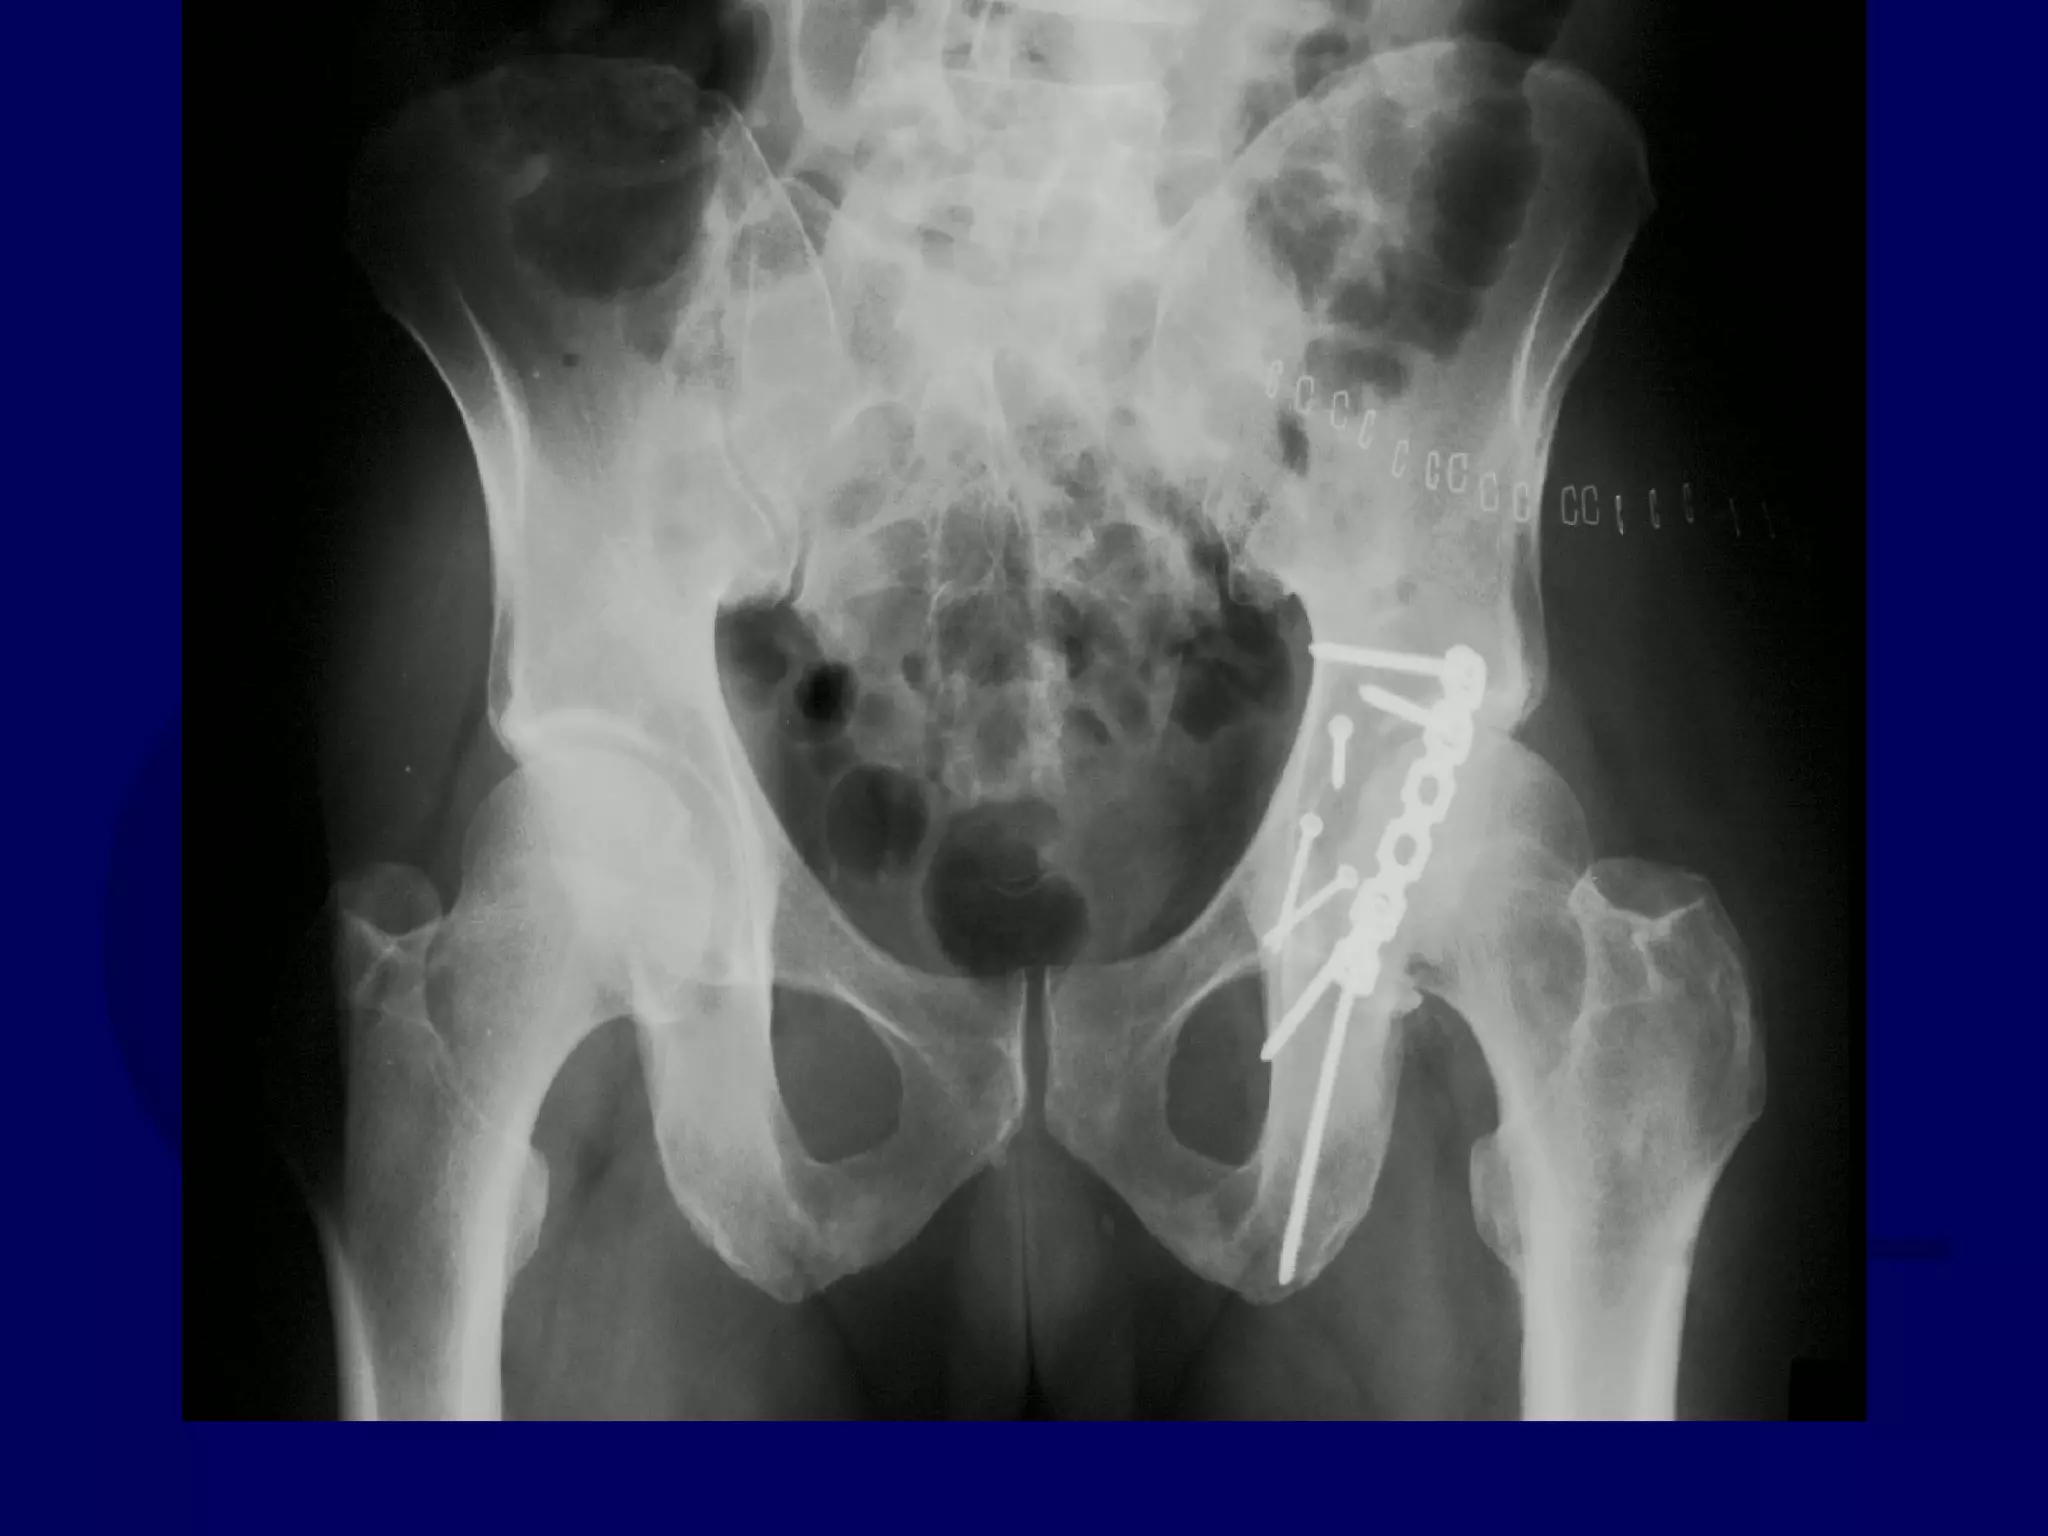

Special Case

“T-Type” Acetabular Fracture

Proximal Femur Fracture

14 y.o. Male

Sequential K-L / Ilioinguinal

Approaches

P.J. 00.12.16

Initial Kocher-Langenbeck

Approach

P.J. 00.12.18

Subsequent Ilioinguinal

P.J. 00.12.22